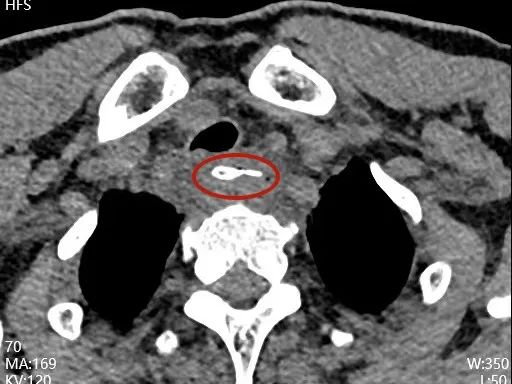

近日,误食鸭骨头 4 天的陈先生因为低烧和吞咽疼痛来到厦门大学附属翔安医院就诊。接诊医生为他安排了食管 CT 检查,CT 显示在食管入口下方卡着一个尖锐且巨大的异物,周围出现积液和气体。

消化内科曾伟副主任医师了解了患者情况后,详细询问病史,仔细查阅 CT 片,发现一根两端带尖角的异物卡在颈部食管,异物大小约 3.5 cm,且已经穿通食管,周围出现细菌感染,形成脓腔。